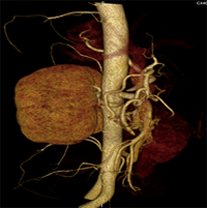

同一病人利用容積數(shù)據(jù)進行三維處理后,高品質MPR和三維圖像上則清晰顯示了縱向排列的腹腔干與腸系膜上動脈相鄰近,血管發(fā)生變 異,近端血管閉塞,為臨床提供了精確的診斷信息。

從上面的例子可以看到,能否為臨床提供高品質的三維影像成為了16層CT的核心價值,而東芝新一代的 全景三維16層CT擁有最為  先進的3項核心技術,在16層核心價值上的表現(xiàn)自然值得期待。